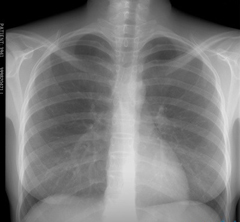

Флюорография легких – исследование органов грудной клетки с помощью рентгеновских лучей, проникающих через легочную ткань и переносящих на пленку посредством флюоресцирующих микроскопических частиц рисунок легких.

Органы грудной клетки по-разному поглощают излучение, поэтому снимок выглядит неоднородным. Сердце, бронхи и бронхиолы выглядят светлыми пятнами, если легкие здоровые, флюорография отобразит легочную ткань однородной и равномерной. А вот если в легких воспаление, на флюорографии, в зависимости от характера изменений воспаленной ткани, будут видны либо затемнения – плотность легочной ткани повышена, либо будут замечены высветленные участки – воздушность ткани достаточно высока.

Результаты флюорографии готовят обычно несколько дней, после этого полученную флюорограмму рассматривает рентгенолог и в том случае если была проведена флюорография здоровых легких, на дальнейшее обследование пациента не отправляют. В противном случае, если рентгенолог обнаружил изменения легочной ткани, человека могут отправить для уточнения диагноза на рентгенографию или в противотуберкулезный диспансер.